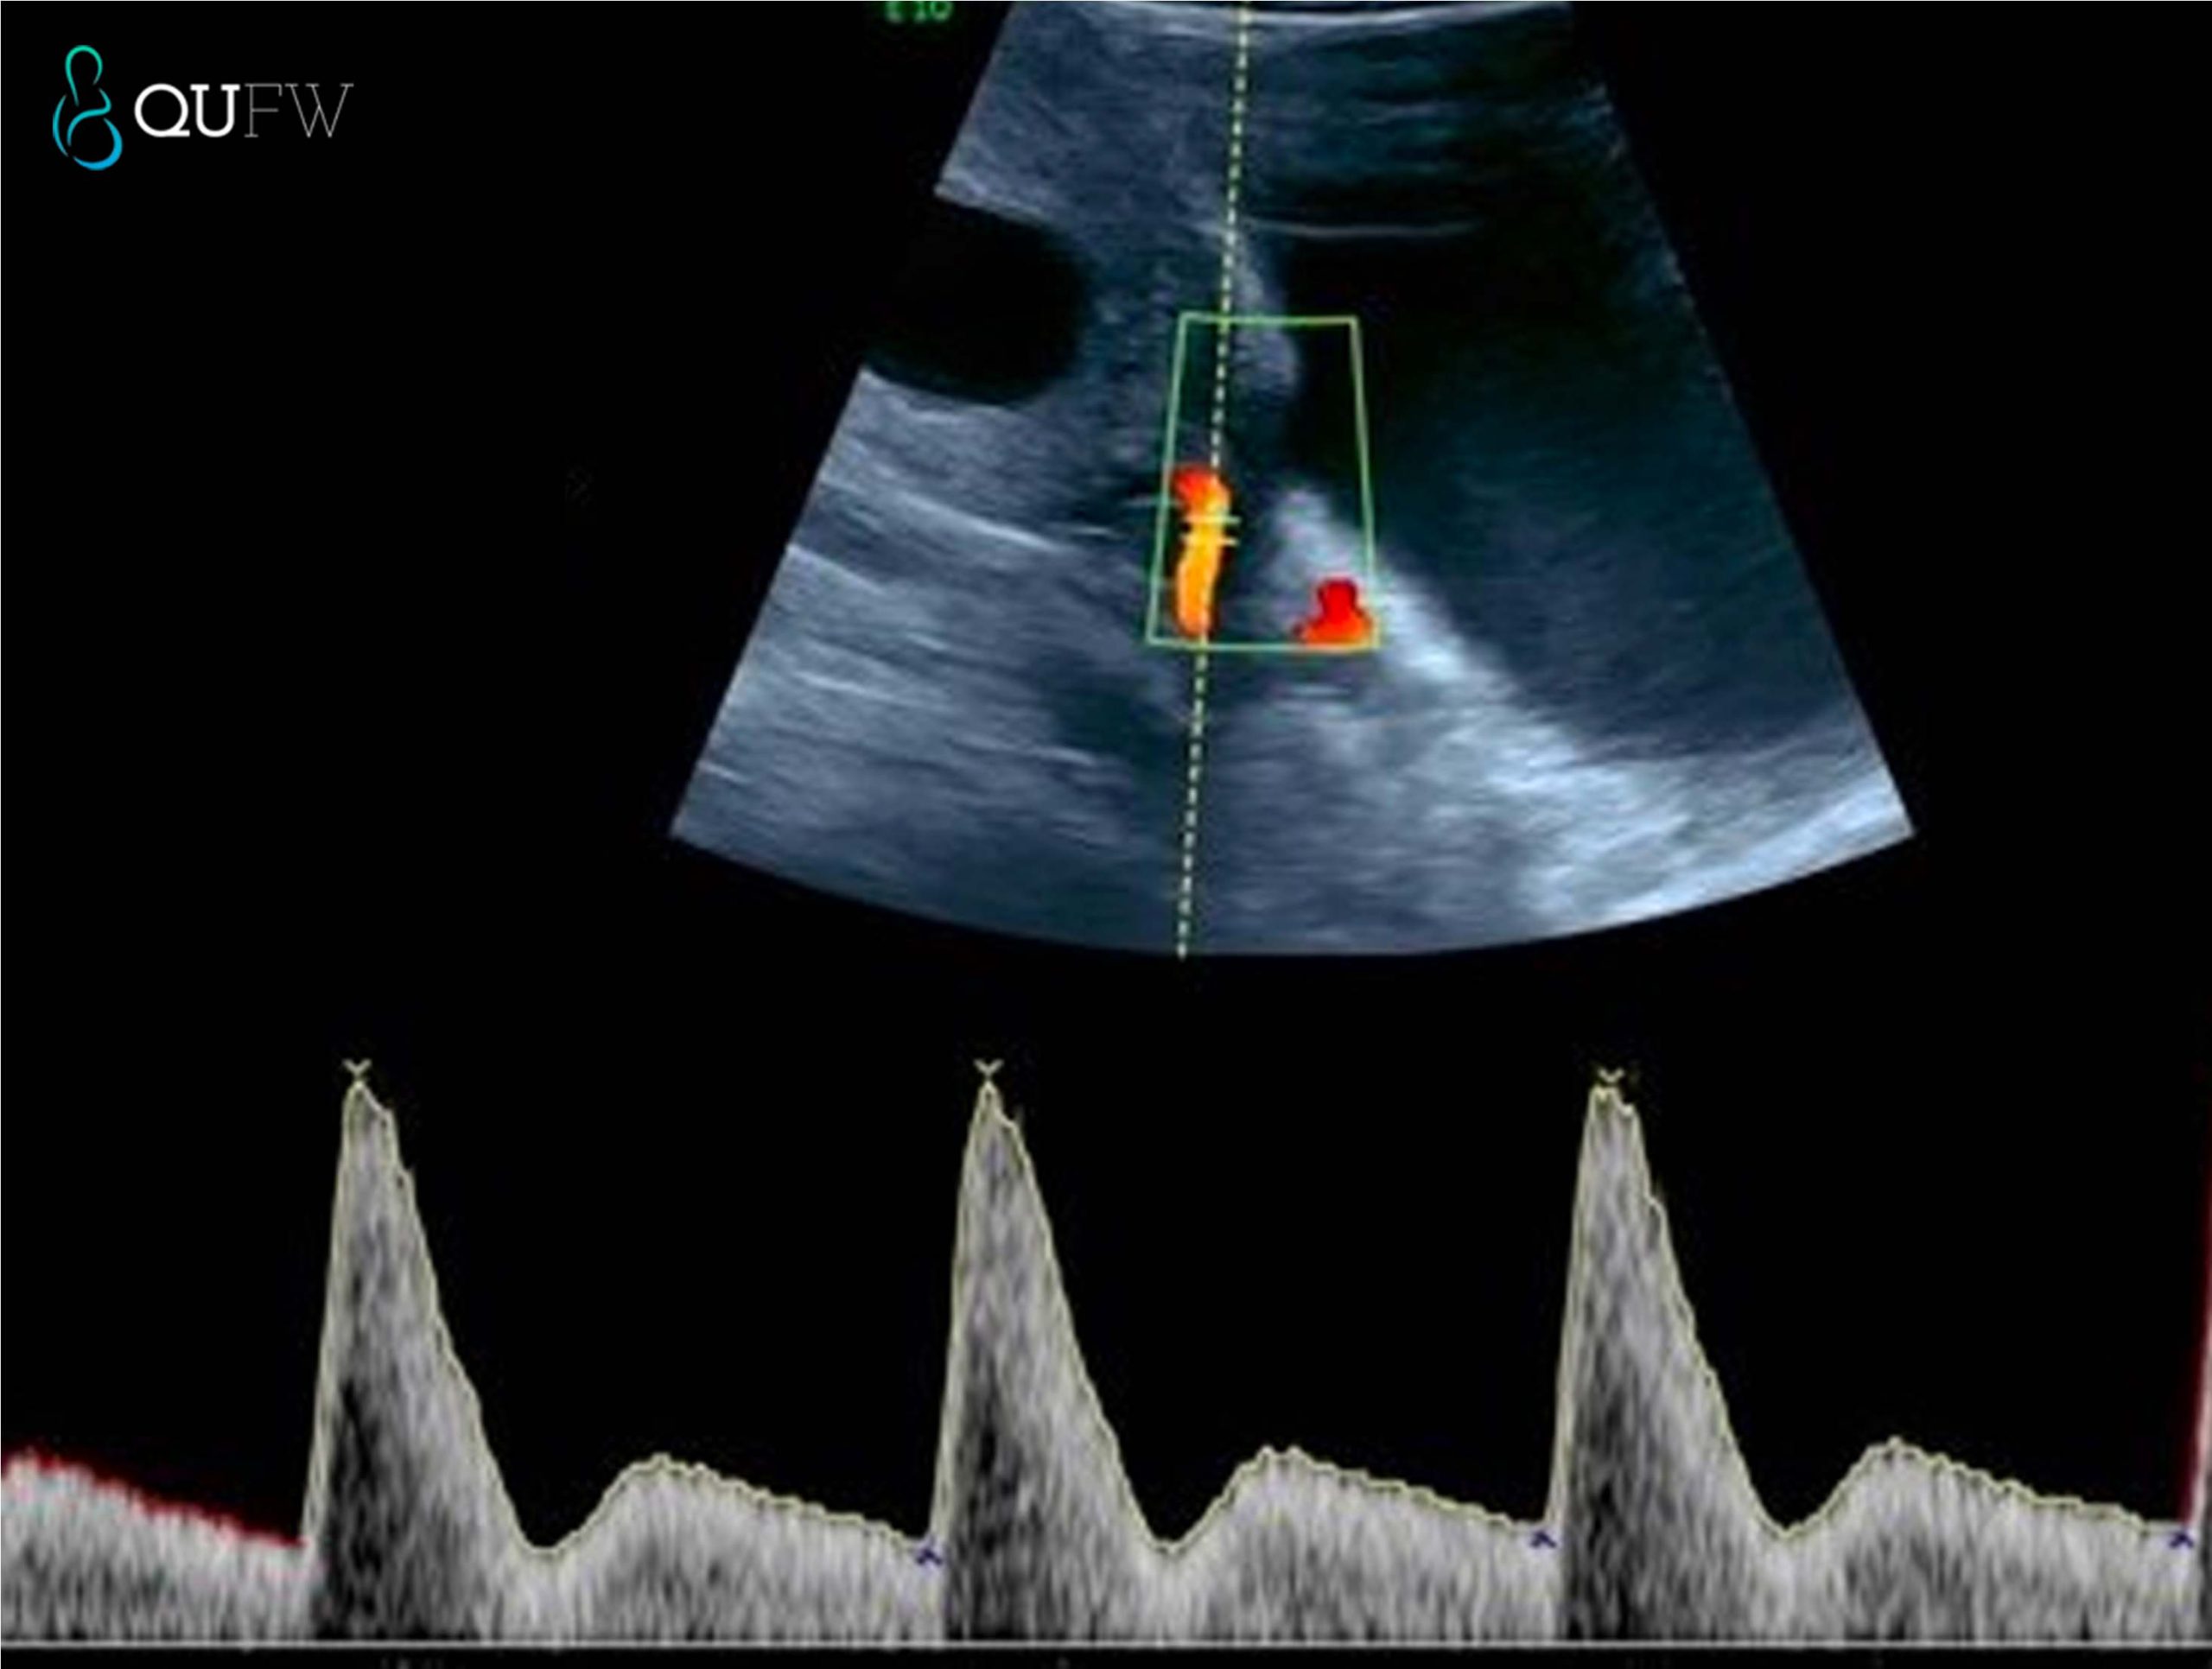

Early onset preeclampsia is an additional screening test that QUFW performs at the Nuchal Translucency/First Trimester Anatomy scan. Hypertension or high blood pressure can develop into a serious medical condition for both the mother and the fetus that may require medication and closer monitoring.

Uterine artery Doppler trace for pre-eclampsia screening assessment